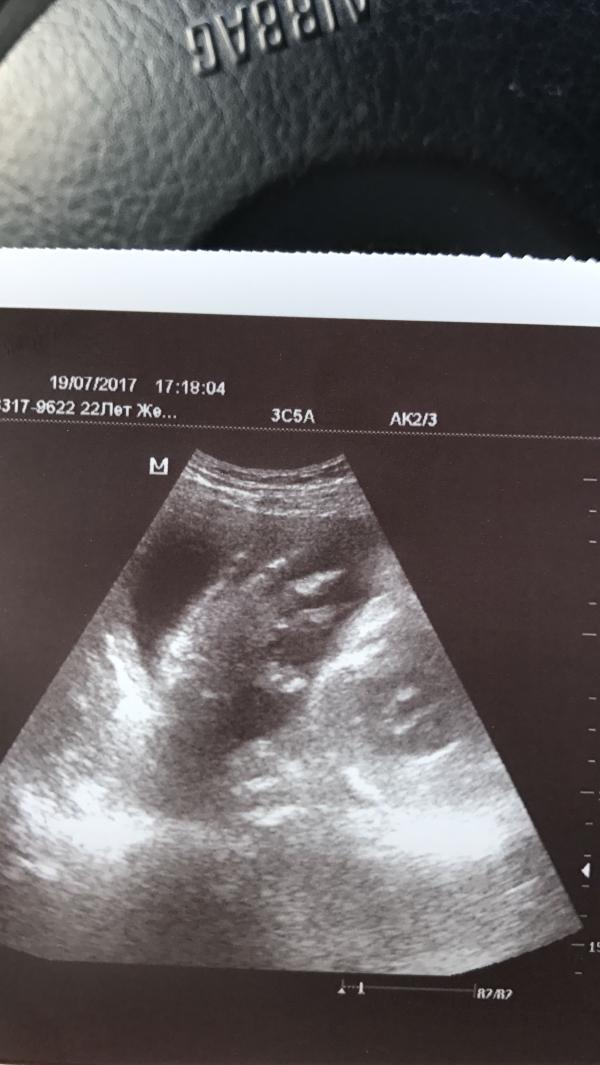

В 31,4 вес 1777)Сказала врач-нормальный вес.

@aigul_aigul, @kotova.m, @olga_rl, @samotesova, @dodaruk.olga1990, @ifill24021982, моя самая мелкая((( 1690 как то меня это напрягает(